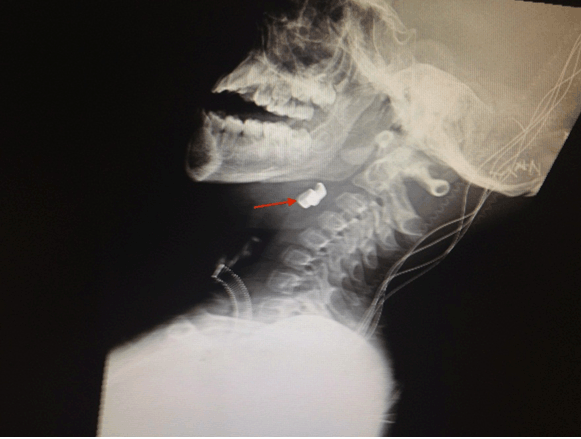

Figure 1: An eight-year-old boy with two radiopaque densities incidentally found on modified barium swallow study. Findings: Two radiopaque objects (red arrow) at the level of the hypopharynx near the cervical esophagus. Technique: Lateral neck soft tissue plain radiograph.

An eight-year-old neurologically devastated boy residing in a specialized nursing home for medically frail children was brought into the emergency department for evaluation of two foreign bodies found incidentally on modified barium swallow study (MBSS). The patient has a history of posterior fossa arteriovenous malformation (AVM) rupture causing large left sided cerebellar hemorrhage that left the patient gastrostomy tube, tracheostomy, and ventilator dependent. Since the AVM rupture, the patient experienced continuous bruxism and tongue biting that required him to wear a mouth guard. The swallow study was performed for evaluation of swallowing prior to advancing his oral intake. Oddly, the patient had been completely asymptomatic with no changes in his ventilator requirements despite the impaction of these foreign bodies. He had been tolerating his gastrostomy tube feeds and did not seem like he was in pain. X-ray of the neck soft tissue lateral view (Figure 1) and anteroposterior view (Figure 2) showed two radiopaque densities ~5–10 mm each, which have the appearance of teeth within the hypopharynx/vallecula at the level of C3 and C4. Consultation to otorhinolaryngology team was initiated. Patient was scheduled for removal in the operating room under general endotracheal anesthesia. The foreign objects were removed under direct visualization with direct laryngoscopy and forceps. The remainder of the laryngoscopic examination was normal. Pathology was consistent with two irregularly shaped shiny golden metallic dental crowns measuring 1.0x0.6x0.6 cm and 1.1x0.8x0.6 cm. A photograph of the dental crowns was taken (Figure 3). It is unclear when our patient lost both his crowns and how long they were in his hypopharynx. However, on chart review, a lateral X-ray of the skull (Figure 4) performed eight months prior to discovery of the foreign bodies on the MBSS showed the two radiographic densities in the same place. This indicates that these dental crowns may have been impacted in the patient's hypopharynx for over eight months. The identification of these two radiographic densities was missed on the initial skull X-ray read. Additionally, a dental consult and examination was performed on the same day as the skull X-ray, which failed to detect the missing dental crowns but showed that his mouth-guard was loose and that teeth 7–10 and 23–26 were mobile/loose.